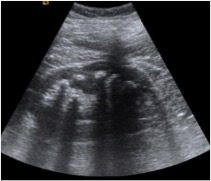

Ecografia:

- Riñón agrandado.

- Focos ecogénicos no dependientes en el parénquima renal o el sistema colector.

- Se diferencian de los litiasis porque no tienen sombra acústicay si artefactos de reverberación, similares a los producidos por el gas intestinal.